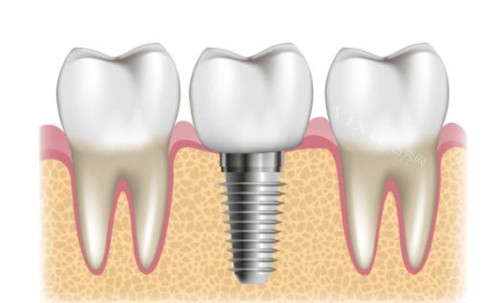

种植牙项目:

国产种植体:4350-6800元/颗

进口种植体:6800-15000元/颗

即刻种植:8000-18000元/颗